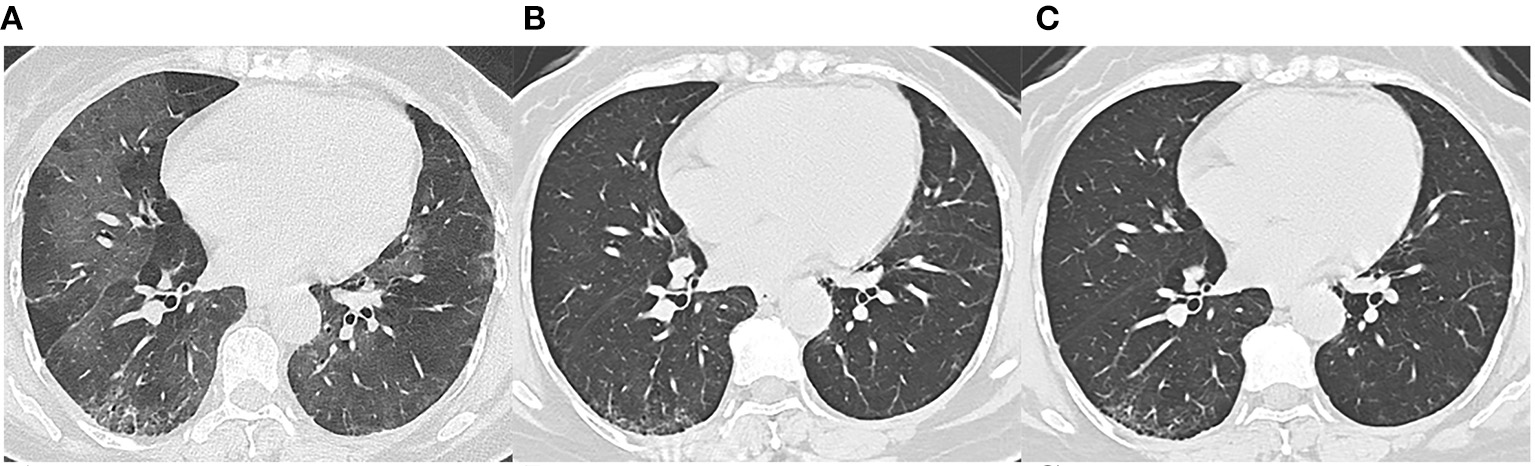

Figure 3

Follow-up chest CT images of a 48-year-old female with COVID-19. (A) At discharge, CT imaging shows crazy paving pattern, parenchymal bands, irregular interfaces, and reticular pattern in bilateral lungs. (B) 3-month follow-up CT shows parenchymal bands, irregular interface, and traction bronchiectasis in the right lower lobe, which indicates fibrosis. (C) The lesions on 7-month follow-up CT are still present. This patient was enrolled in fibrosis group.

We reviewed three CT scans for each patient. The average interval between discharge and latest follow-up was 219 days, and the average intervals of the two subgroups did not differ statistically (p = 0.066). The dynamic changes of chest CT features were listed in Table 2. As shown in Table 2, the predominant chest CT features observed at discharge included parenchymal band (73%), GGO (71%), interlobular septal thickening (68%), consolidation (46%), and irregular interface (46%). The less common CT features included reticular pattern (39%) and traction bronchiectasis (29%). The rare CT features were air bronchogram (7%) and crazy paving pattern (5%). Quantitative CT parameters calculated by the artificial intelligence software revealed that the median opacity score was 4.0 (IQR 2.0–5.0), the median volume of opacity was 178.0 ml (IQR 41.4–422.0 ml), and the median percentage of opacity was 4.3% (IQR 1.0%−12.4%). After discharge, all the quantitative CT parameters gradually decreased with time. The median opacity score, volume of opacity, and percentage of opacity on the latest follow-up CT (7 months after discharge) were decreased to 0.0 (IQR 0.0–1.0), 0.9 (IQR 0.0–12.8) ml, and 0.0% (IQR 0.0–0.3%), respectively. Twenty-five patients (61%) achieved complete radiological resolution on the 7-month follow-up CT. GGO (12%) and consolidation (10%) were almost resolved on the 7-month follow-up CT, while evidence of fibrosis, such as parenchymal band (41%), interlobular septal thickening (32%), reticular pattern (12%), and traction bronchiectasis (29%), were still obvious (Figures 2, 3).

However, the CT manifestations of pulmonary fibrosis (interlobular septal thickening, irregular interface, parenchymal band, and traction bronchiectasis) were still apparent on the 7-month follow-up CT. As reported, pulmonary fibrosis may develop in the early stage in discharged patients with SARS (11), and the fibrosis may be long-persistent (15), whereas the pulmonary fibrosis in discharged COVID-19 patients may be absorbed with time (6), which was consistent with our study (Figure 2). The reversibility of fibrosis probably indicated that the pulmonary fibrosis on chest CT did not signify actual pathologic fibrosis (14), and thus whether these lesions would completely disappear required further observation.